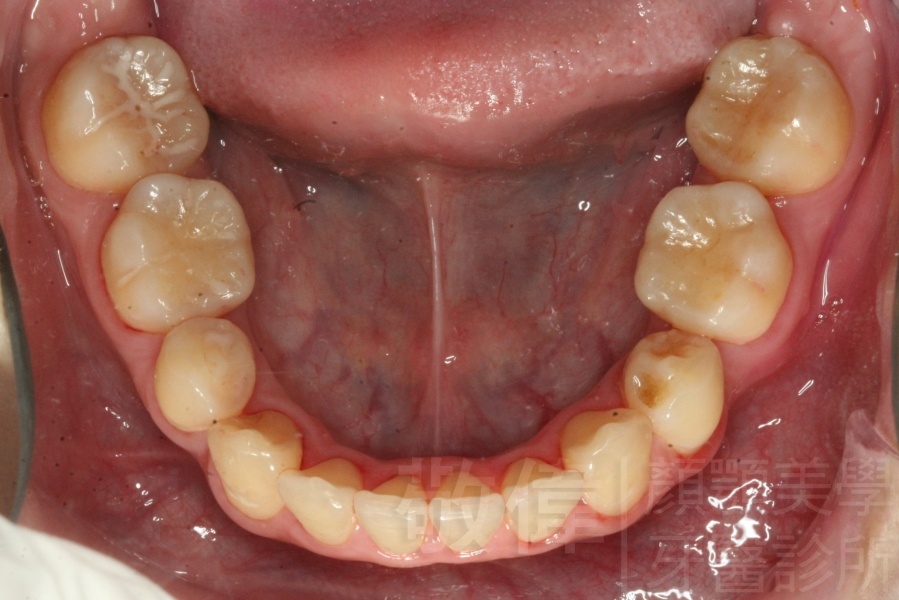

齒顏矯正/上顎暴牙且牙齒極度混亂

矯正前-上   矯正前-下

<個案說明>

上顎暴牙且牙齒極度混亂,經由矯正之後,臉型大幅度改善,牙齒的排列更加的整齊健康。相較於之前眼神充滿精神,自信心展現無遺。